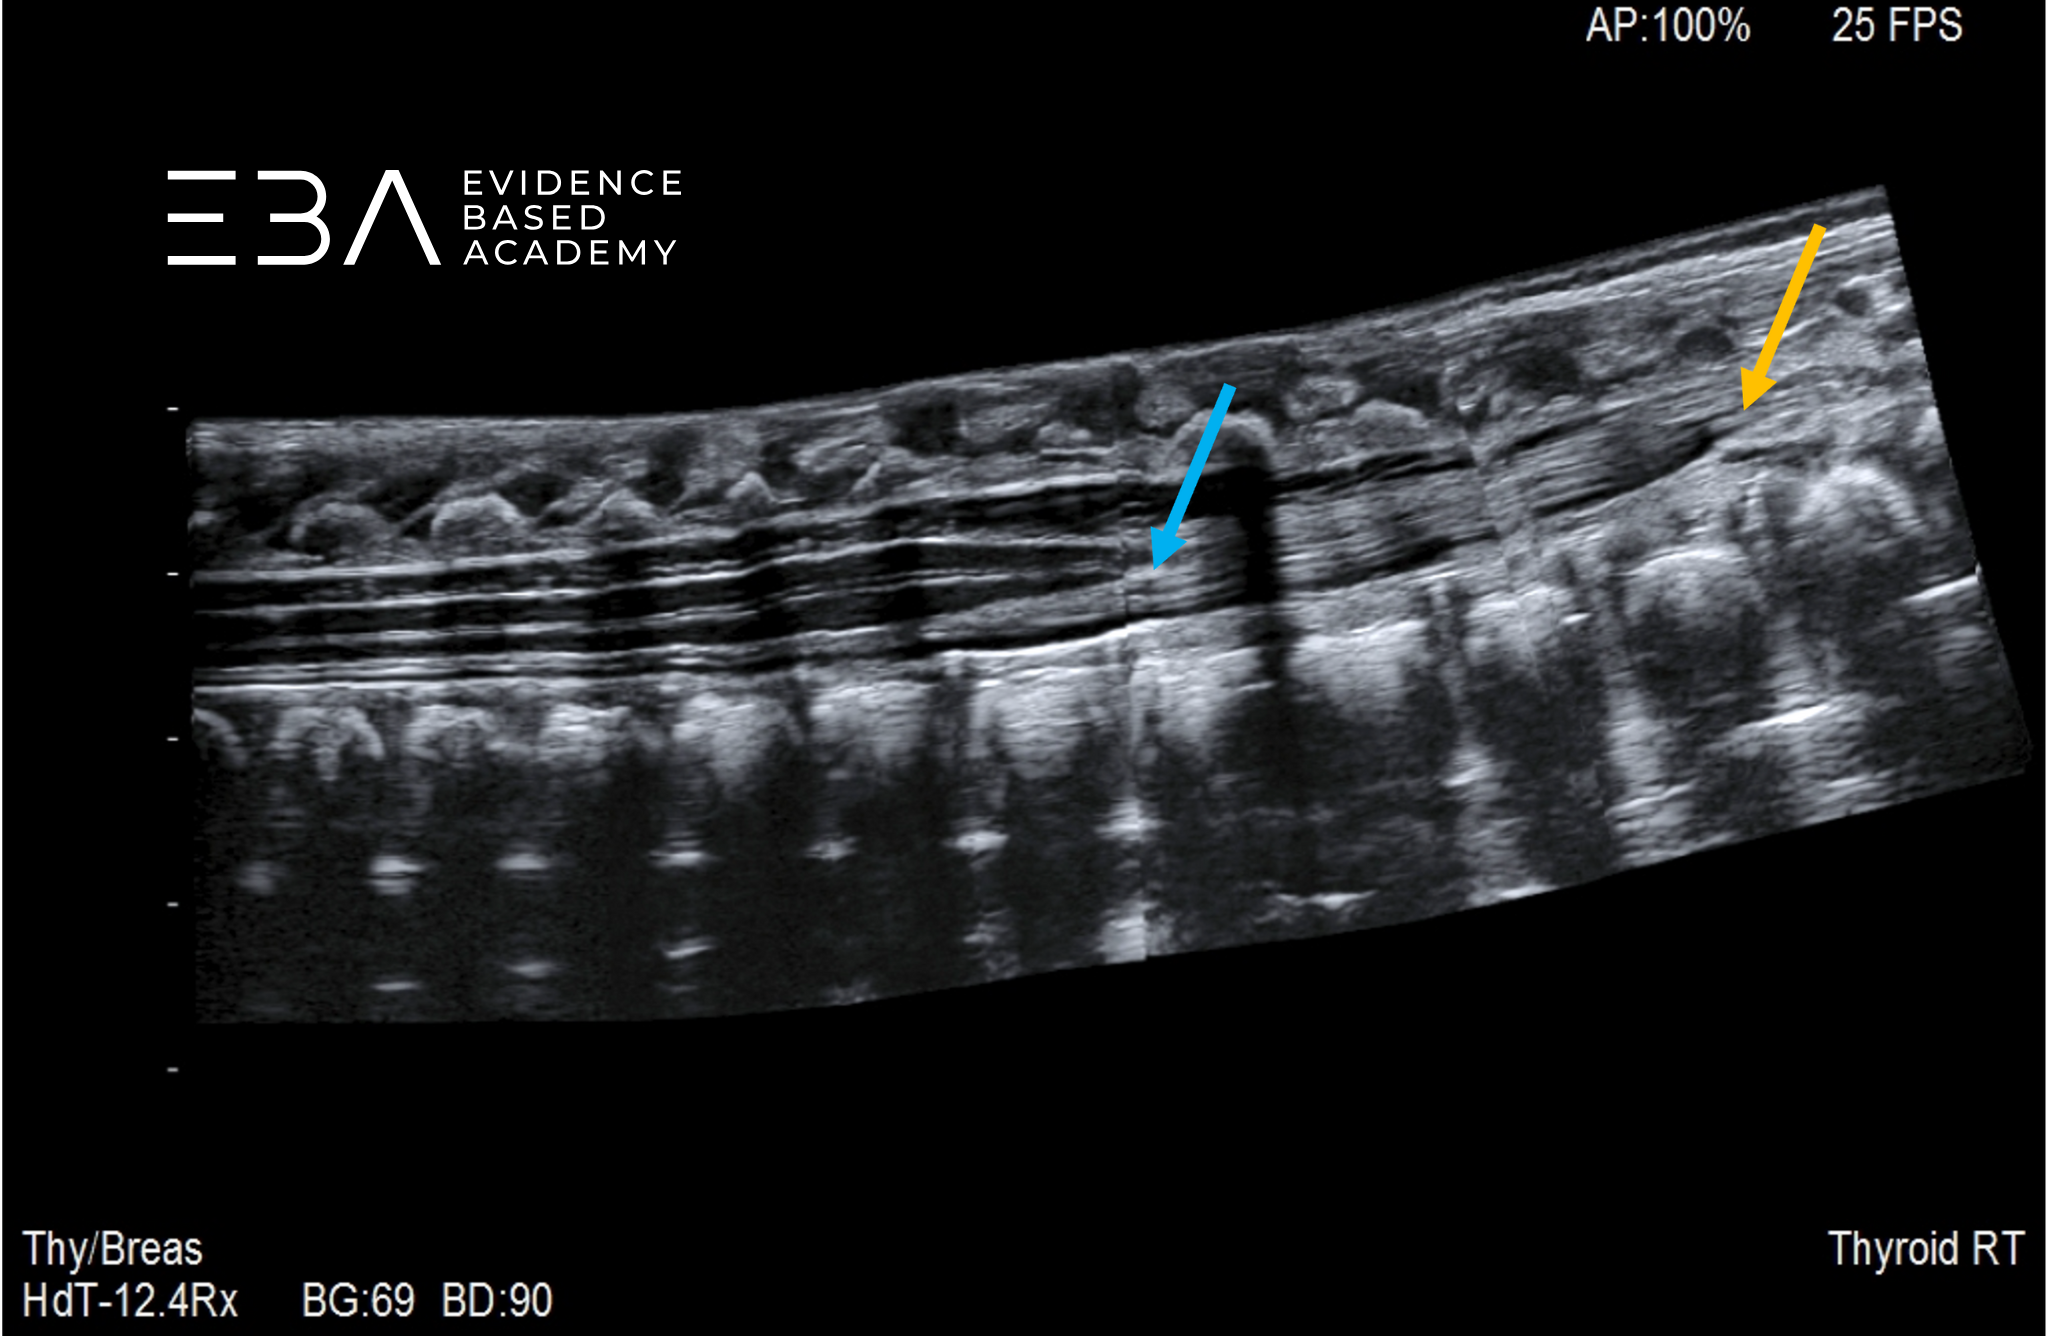

fot. 1

Przekrój podłużny kanału kręgowego – obrazowanie panoramiczne.

USG panoramiczne z rozszerzonym polem widzenia może obrazować długie odcinki kręgosłupa i znacznie ułatwia identyfikację poziomu kręgowego.

fot. 8

Przekrój podłużny kanału kręgowego – obrazowanie panoramiczne. Niebieską strzałką zaznaczono koniec stożka rdzenia kręgowego, pomarańczową strzałką zaznaczono koniec worka oponowego.

fot. 9

Przekrój podłużny kanału kręgowego – obrazowanie panoramiczne. Numeracja kręgów.